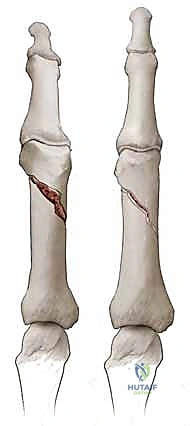

- كسور السلامية القريبة (Proximal Phalanx Fractures): غالباً ما تتخذ هذه الكسور زاوية راحية (Apex Volar Angulation). يحدث هذا لأن العضلات بين العظام (Interosseous muscles) تسحب الجزء القريب من الكسر نحو الثني، بينما تسحب آلية الباسطة الجزء البعيد نحو المد.

- كسور السلامية الوسطى (Middle Phalanx Fractures): يعتمد اتجاه الانزياح هنا على موقع الكسر بالنسبة لمكان التصاق الوتر القابض السطحي (FDS). إذا كان الكسر قريباً من الالتصاق، فإن الجزء البعيد ينثني. وإذا كان الكسر بعيداً عن الالتصاق، فإن الجزء القريب ينثني.

في الكسور المفتتة أو المعقدة، يقوم الدكتور هطيف بعمل شق جراحي دقيق (غالباً من الجانب لتجنب الأوتار الظهرية) لكشف الكسر وإعادة ترتيب الشظايا العظمية بدقة متناهية، ثم تثبيتها باستخدام:

* البراغي الساحبة (Lag Screws): تُستخدم في الكسور المائلة الطويلة أو الحلزونية لتوفير ضغط قوي بين حواف الكسر.